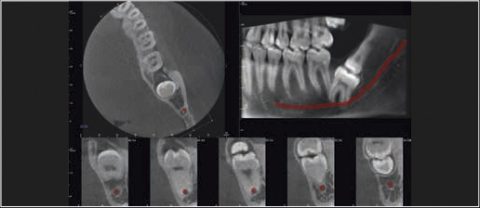

Tomografia komputerowa jest niezastąpiona w planowaniu leczenia implantologicznego i chirurgicznego. W wielu przypadkach pozwala uniknąć powikłań podczas leczenia kanałowego jeszcze przed jego rozpoczęciem. Wysokiej rozdzielczości badanie mikroCBCT (endoCBCT) precyzyjnie obrazuje architekturę systemu kanałowego zęba. Na jego podstawie lekarz może ocenić ilość kanałów, ich krzywiznę oraz ewentualne połączenia.

Cztery różne pola obrazowania zapewniają niezawodną diagnostykę 3D w całym obszarze jamy ustnej. Zapewniają one precyzyjne dopasowanie, odpowiednie do wskazań a także uniwersalne możliwości zastosowania w codziennej praktyce – od endodoncji, poprzez implantologię do chirurgii jamy ustnej.